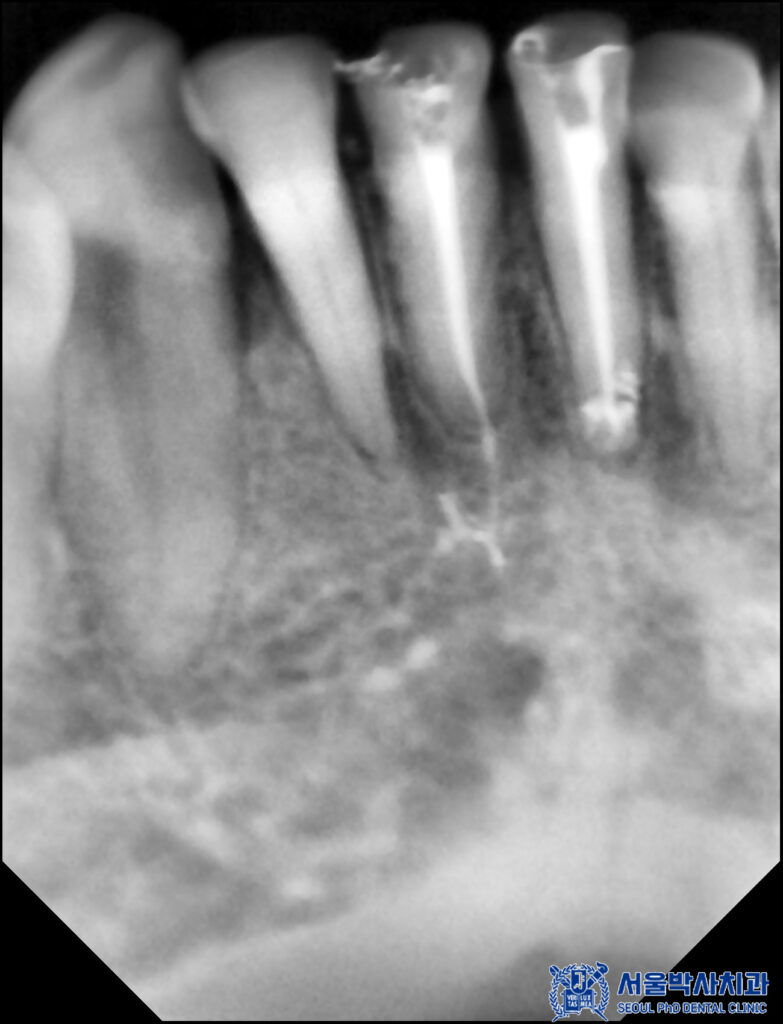

먼저 앞니 치료를 진행했습니다.

재신경치료는 이미 신경치료를

한번 했던 곳에 또 다시

신경치료를 진행하는 것이기에

일반적인 신경치료보다 까다로워서

신경치료는 미세한 치아 신경관

하나하나 찾아내어 살리는 진료이기에

산성역치과 서울박사는

MTA 신경치료를 진행하고 있습니다.

본원은 MTA라는 바이오세라믹 성분을 사용하여

신경치료를 하고 있습니다.